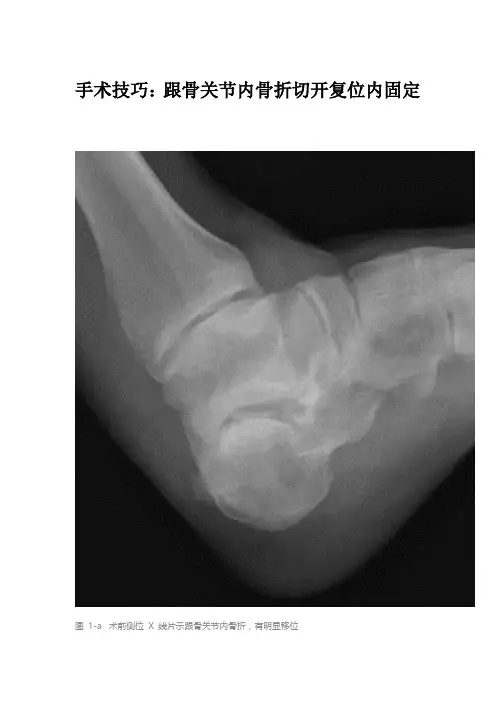

手术技巧:跟骨关节内骨折切开复位内固定图1-a 术前侧位X 线片示跟骨关节内骨折,有明显移位图 1-b 术前斜位 X 线片示跟骨有移位的关节内骨折图 1-C 术前 CT 矢状位片示移位的跟骨关节内骨折图 1-D 术前 CT 轴位片示移位的跟骨关节内骨折图 1-E 术前冠状位 CT 可见有移位的跟骨关节内骨折,箭头所指为压缩的骨折块图1-F 患者侧卧,跟骨切开复位内固定术前垫好沙袋。